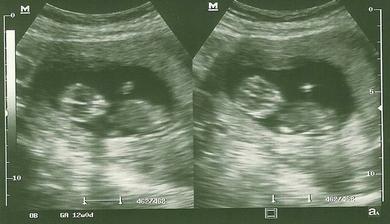

Naše druhé :o)

51 mm od hlavicky po zadok :o) a ty??